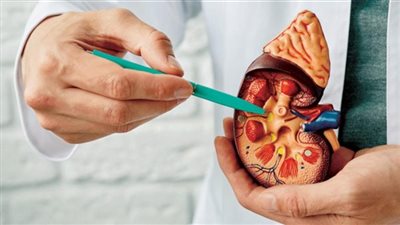

استشاري يكشف 4 مراحل للإصابة بسرطان الكلى.. وهذه أبرز الأعراض

يعتبر سرطان الكلى من ضمن أنواع السرطانات التي تصيب في الغالب الرجال عن النساء، وخاصة في سن من 50 لـ 70 عاما، حيث يتم تصنيف سرطان الكلى وفقًا لمدى تقدم السرطان ومدى انتشاره في الجسم.

ويمر سرطان الكلى بـ 4 مراحل، حيث يستعرض موقع «صحة 24»، التفاصيل الكاملة حول هذا الأمر، وفقا لاستشاري أمراض الكلى بمستشفى CK Birla (R)، دلهي، الدكتور فيكرام كالرا.